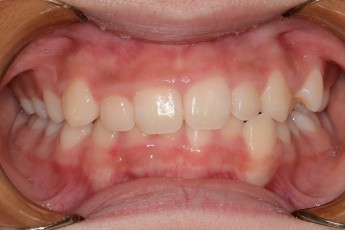

BEFORE & AFTER

- 덧니교정